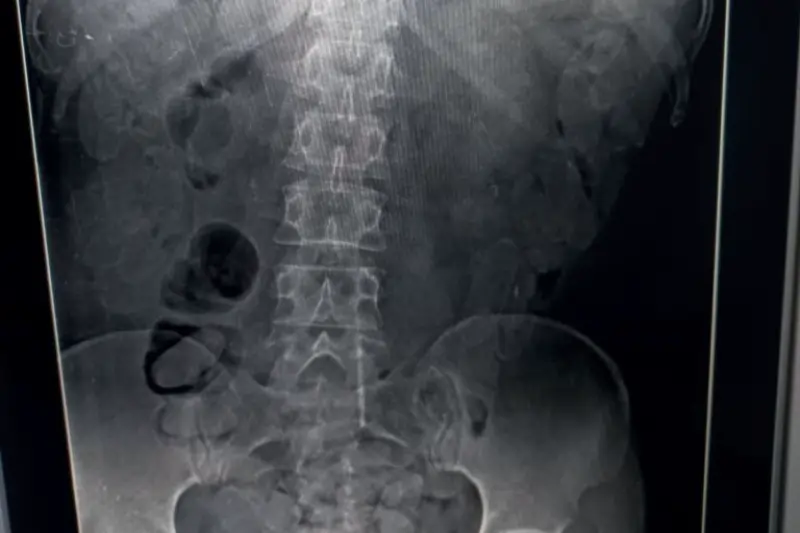

Casal boliviano expeliu 192 cápsulas de cocaína após três dias internado no Hospital das Clínicas de Marília

O casal boliviano preso na última quarta-feira (2) por envolvimento em tráfico internacional de drogas expeliu, ao longo de três dias, 192 cápsulas de cocaína no Hospital das Clínicas de Marília. A informação consta no boletim de ocorrência e foi confirmada por fontes ligadas à investigação. Ingestão foi feita na fronteira com destino ao interior […]

Casal boliviano é preso transportando cocaína em ônibus

Um casal de estrangeiros foi preso na manhã desta quarta-feira (2) ao ser flagrado transportando drogas no estômago. A abordagem aconteceu durante uma operação da Polícia Militar Rodoviária na rodovia Rachid Rayes (SP-333), em Marília. Os suspeitos estavam em um ônibus que fazia a rota entre Campo Grande (MS) e Belo Horizonte (MG). Durante a […]